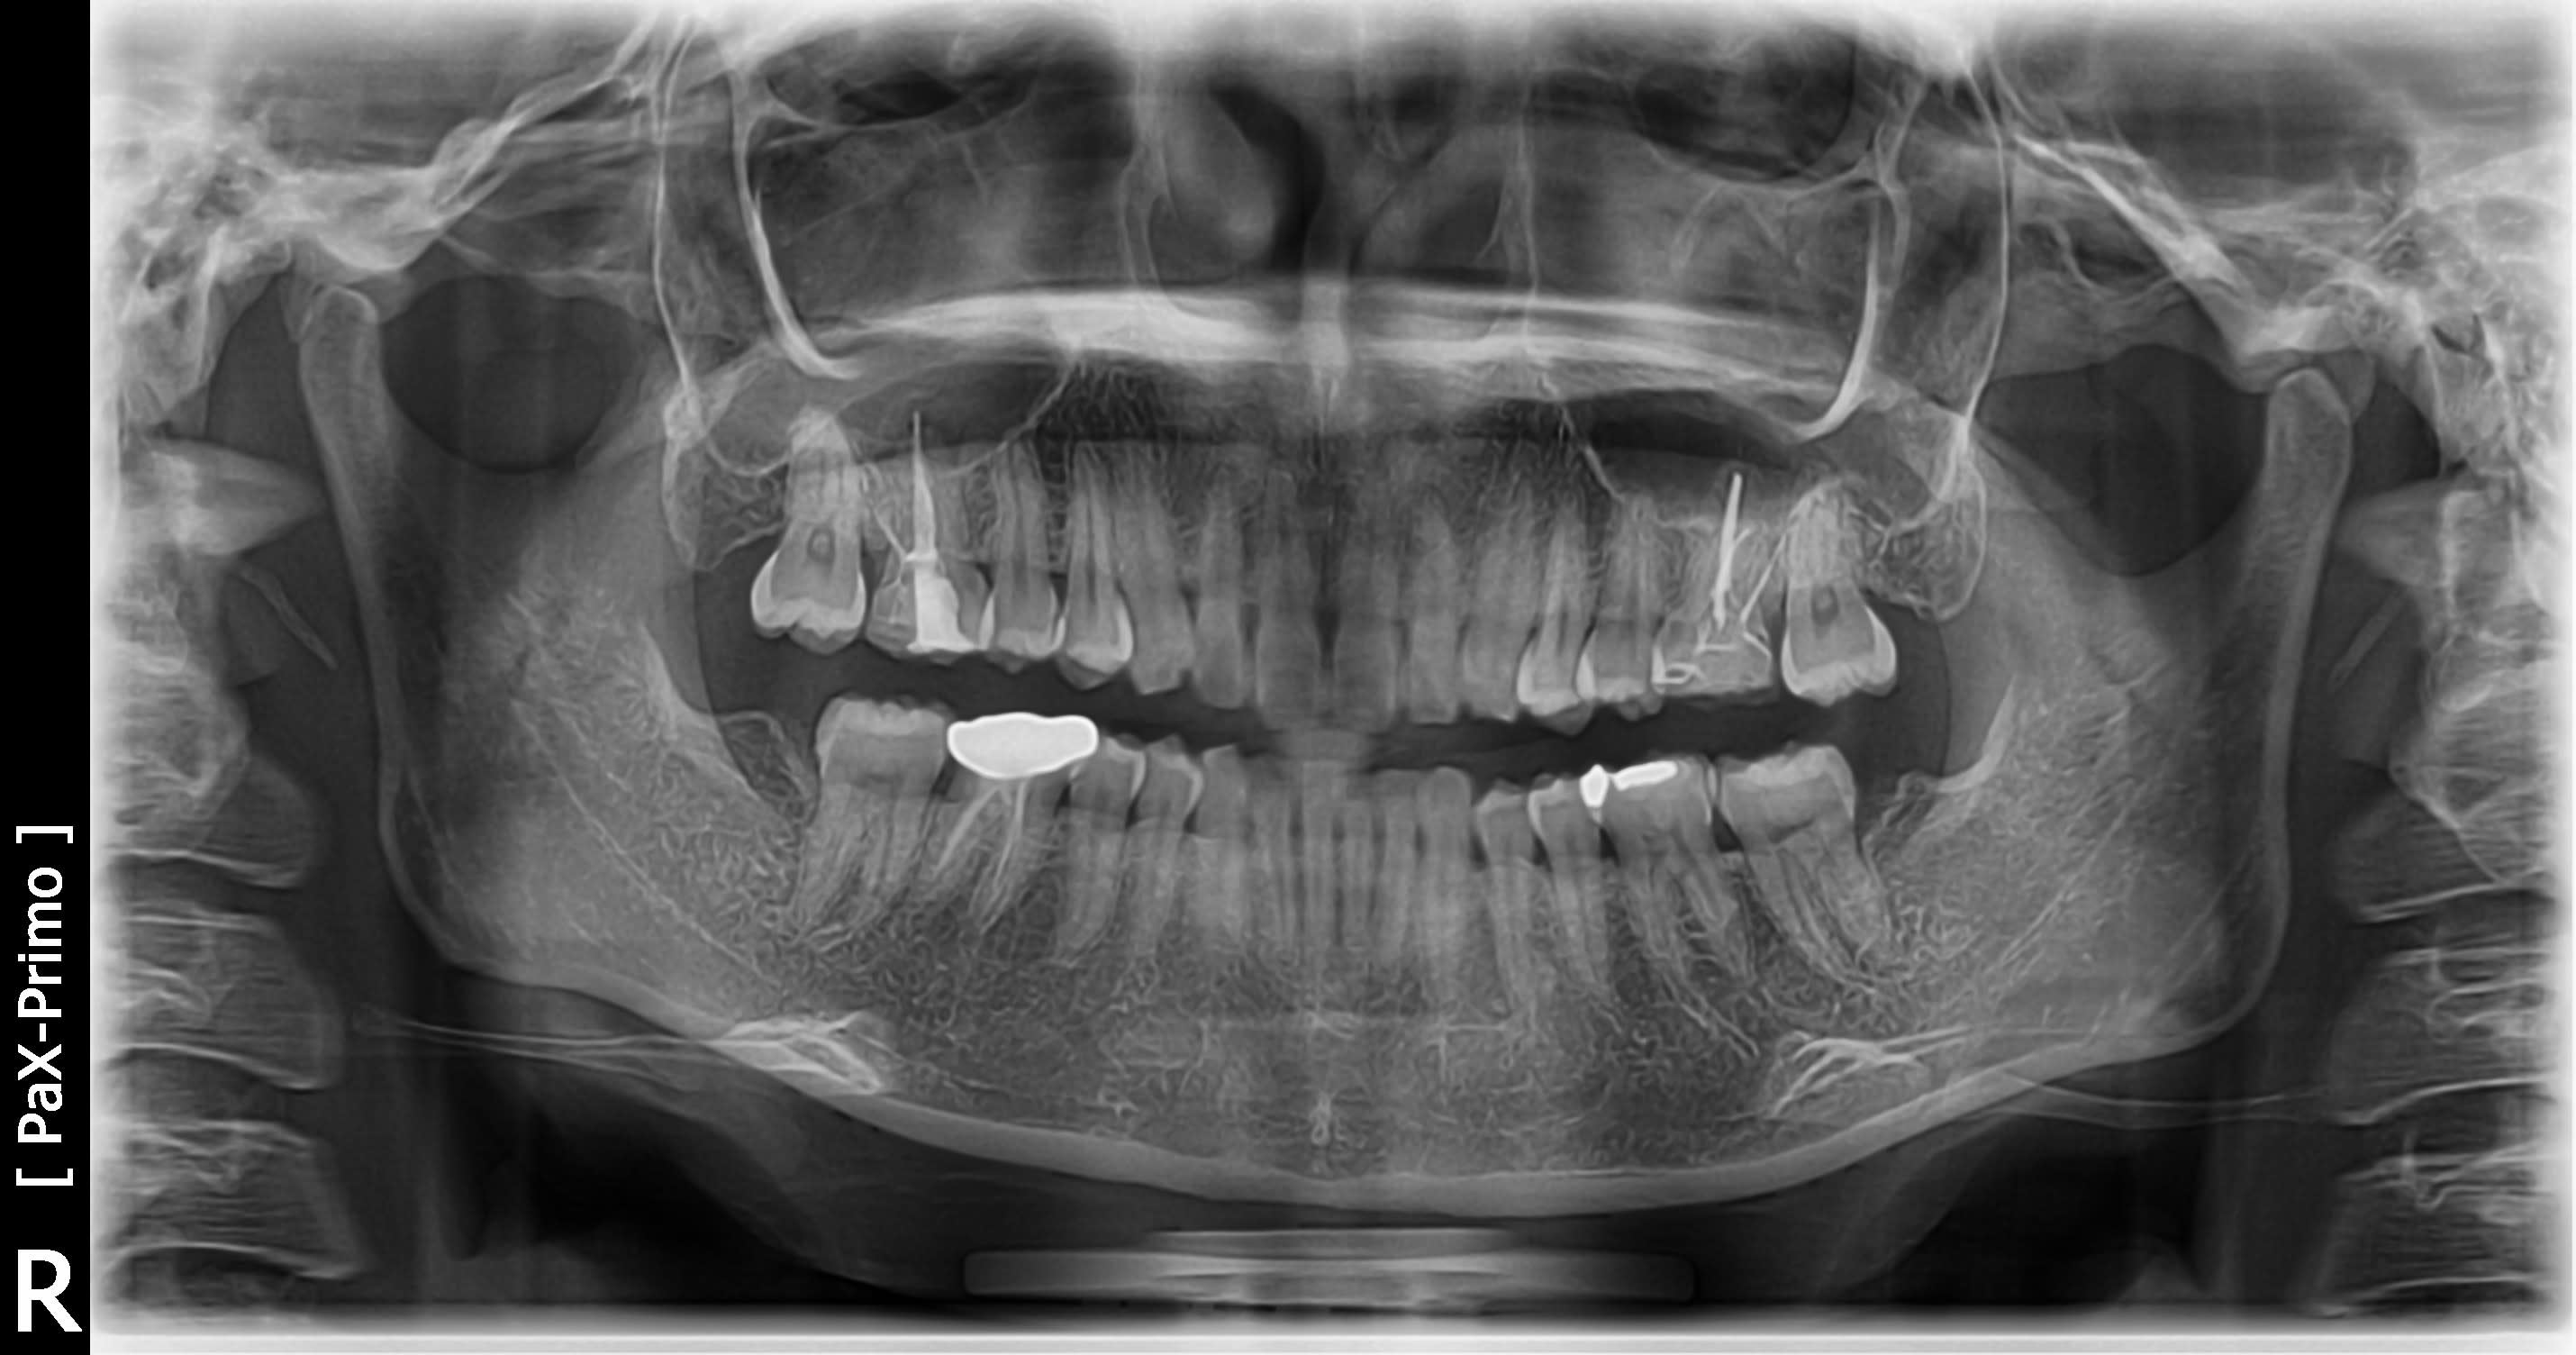

La patiente de 25 ans presente un bruxisme nocturne avec abrasion selective des canines maxillaires.

ce cas est tres simple , l'usure des canines est due à la couronne en metal . tu l'enleves ,tu lui fais un prov , et on en parle plus . ç est 1 pb de décalage latéral en OIM .

tu remarqueras que les 2 canines sont usées de façons différentes .

celle de droite est 1 usure par mouvement de grande amplitude alors que celle de gauche ,non .

et comme par hasard , ç est celle de droite qui est usée par le + grand mouvement , comme pour s'ecarter le plus possible de la 36 .

Mais mais mais , si tu perturbes le trajet d'entrée de fermeture par une couronne iatrogène , qui modifie cet équilibre instable en latéral , 1 des canines se trouvera en sur verrouillage ( ta 43 ? ) et l'autre en sur guidage ( ta 33 ?) .

tu rigoles ou quoi ? t'as vu la tronche des 6 ?

- en distal de 26 il y a une prematurité , sa face vest est mangée et la 27 est à l'ouest

- la 16 est toute usée

- tu es presque en supra-clusion par usure des calages post

- quant au décalage latéral il n'a pas besoin d'etre grand donc visible au niveau inter incisif , pour induire un bruxisme . surtout qu'elle est encore jeune .

Les 6 ont cette tete car la patiente a eu des inlays onlays en cerec sur 16/26 depuis une 10aine d'annees.

Ah ok maintenant je vois! Mais c'est plus 37 et 47 qui sont en vestibuloposition non?